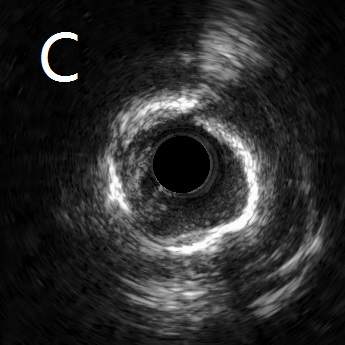

患者为77岁女性。因冠心病进行冠状动脉介入治疗,血管造影示冠状动脉前降支闭塞,且伴有严重钙化(图A)。经过不懈努力,导丝最终顺利通过闭塞段,并于闭塞段先行使用球囊扩张进行病变预处理。然而,坚硬致密的钙化斑块导致预扩球囊无法行病变充分扩张,球囊“狗骨头”症明显(图B),此时直接植入支架,通常会出现支架膨胀不良,难以维持血管管腔,无法保证患者预后。遂采用血管内超声对病变处进行检测,提示病变处存在严重的360度环形钙化(图C、D)。